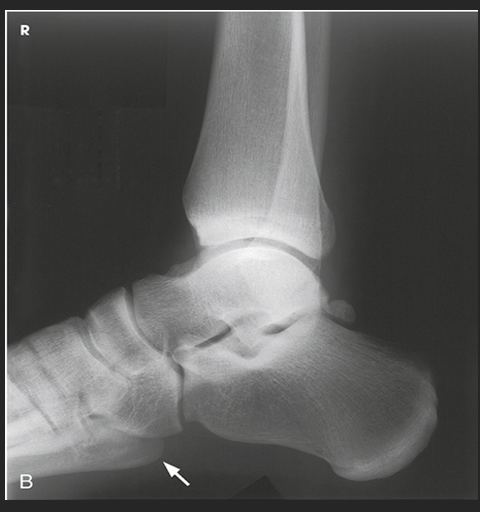

Name this projection.

Lateral ankle

What type of projection is it?

Mediolateral

Which side is the patient turned toward?

Affected side

Where does the CR enter?

Perpendicular to the ankle joint, entering at the medial malleolus

How do you evaluate for a true lateral?

The tibiotalar joint will be well visualized, and the fibula will be over the posterior half of the tibia

How much of the distal tibia and fibula must be included?

1/3

Which joint is well visualized?

Tibiotalar